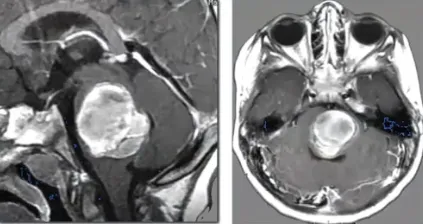

一名3岁半患儿因脑干海绵状血管瘤破裂出血形成巨大血肿,紧密包裹脑干,导致出现严重右侧偏瘫。患儿无法独立站立行走,幼龄即面临重大生命威胁。

转诊至巴教授所在医院后,女孩家属于手术室外焦急等候。巴教授通过颞颞下入路谨慎抵达桥脑侧面,最终成功清除血肿,并完整保留桥脑后方结构。此举对患儿未来生活质量至关重要,意味着术后不会产生额外功能损伤。